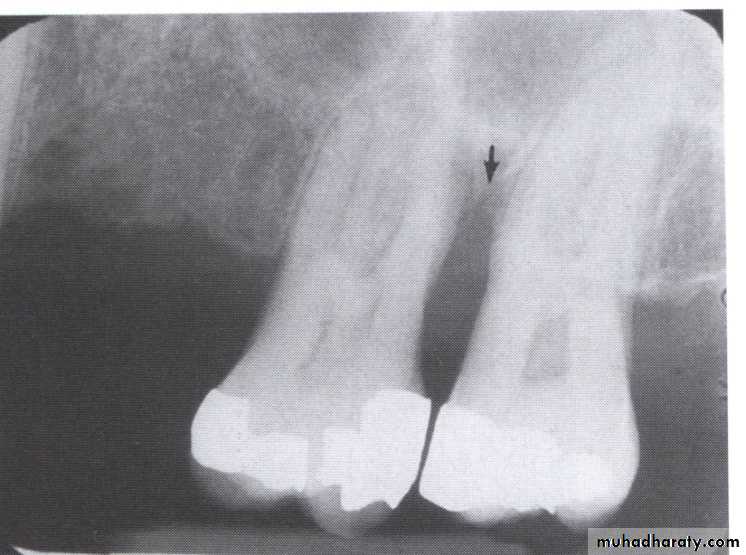

Vertical osseous defects can be divided into two primary types: Interproximal crater is a two-walled, trough like depression

that forms in the crest of the interdental bone between adjacent teeth.

The Infrabony defect is a vertical deformity within bone that extends apically along the root from the alveolar crest.

Often infrabony defects are difficult or impossible to recognize on a radiograph because one or both of the cortical bony plates remain superimposed with the defect.

Clinical and surgical inspections are the best means of determining the number of remaining

bony walls.

Visualization of the depth of pockets

may be aided by inserting a gutta-percha

point.